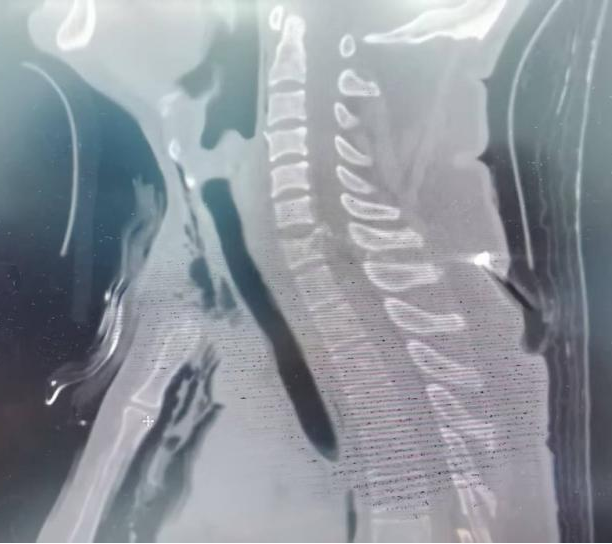

据悉,该患者在使用射钉枪作业时不慎发生意外,一枚高速射钉由其颈前正中区射入,依次贯穿气管和颈椎,最终自颈后穿出,仅钉尾残留于皮下。伤后患者颈部剧痛,四肢当即无法活动,经120送至当地医院,初步包扎并拍摄X光片提示“颈部贯通伤”。因伤势危重,患者被紧急转往省立医院奥体院区急救中心。

CT检查显示,射钉呈前后走向贯穿颈部正中,伤及气管与颈椎,合并纵隔气肿和肺挫裂伤。气管破损处出血易致误吸,危及生命;更严重的是,C7节段颈髓遭受贯穿损伤,伴随高位瘫痪,可能进一步影响呼吸与心跳功能。此外,钉道走向提示食管损伤风险极高。经创伤中心主任医师张鹏、副主任医师赵宝、主治医师赵之孟,耳鼻喉科副主任医师高昆、胸外科主治医师李猛等多学科专家会诊,迅速制定分阶段救治方案:先行气管切开缓解呼吸衰竭,再限期经颈后路行椎管清创减压及内固定术,以控制中枢感染风险。